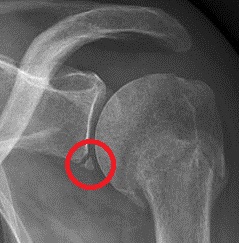

- Eine Schädigung des Labrum, die als Bankart-Läsion bezeichnet wird (4). Wenn sich der Oberarmknochen nach vorne verschiebt, kann es auch zu einer Verletzung der Faserknorpelschale kommen, die den Oberarmknochen in seiner Position hält.